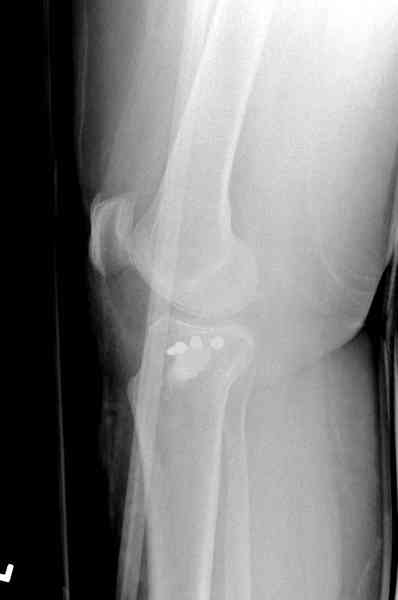

Из медиального окна можно приподнять латеральную

импрессию. Фиксация тремя параллельными шурупами в

эпифизарной части над импрессией. Создается крыша,

которая предупредит коллапс. На образовавшуюся полость - костная

пластика из аутокости или синтетический заменитель. Мы применяем

Osteoset в 4-5 мм диаметре таблеточки или иньекционную форму Prodens.